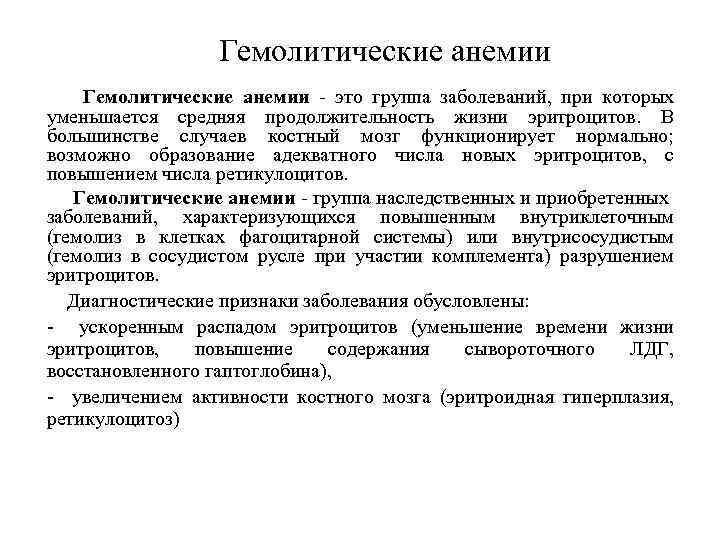

Гемолитические анемии Гемолитические анемии - это группа заболеваний, при которых уменьшается средняя продолжительность жизни эритроцитов. В большинстве случаев костный мозг функционирует нормально; возможно образование адекватного числа новых эритроцитов, с повышением числа ретикулоцитов. Гемолитические анемии - группа наследственных и приобретенных заболеваний, характеризующихся повышенным внутриклеточным (гемолиз в клетках фагоцитарной системы) или внутрисосудистым (гемолиз в сосудистом русле при участии комплемента) разрушением эритроцитов. Диагностические признаки заболевания обусловлены: - ускоренным распадом эритроцитов (уменьшение времени жизни эритроцитов, повышение содержания сывороточного ЛДГ, восстановленного гаптоглобина), - увеличением активности костного мозга (эритроидная гиперплазия, ретикулоцитоз)